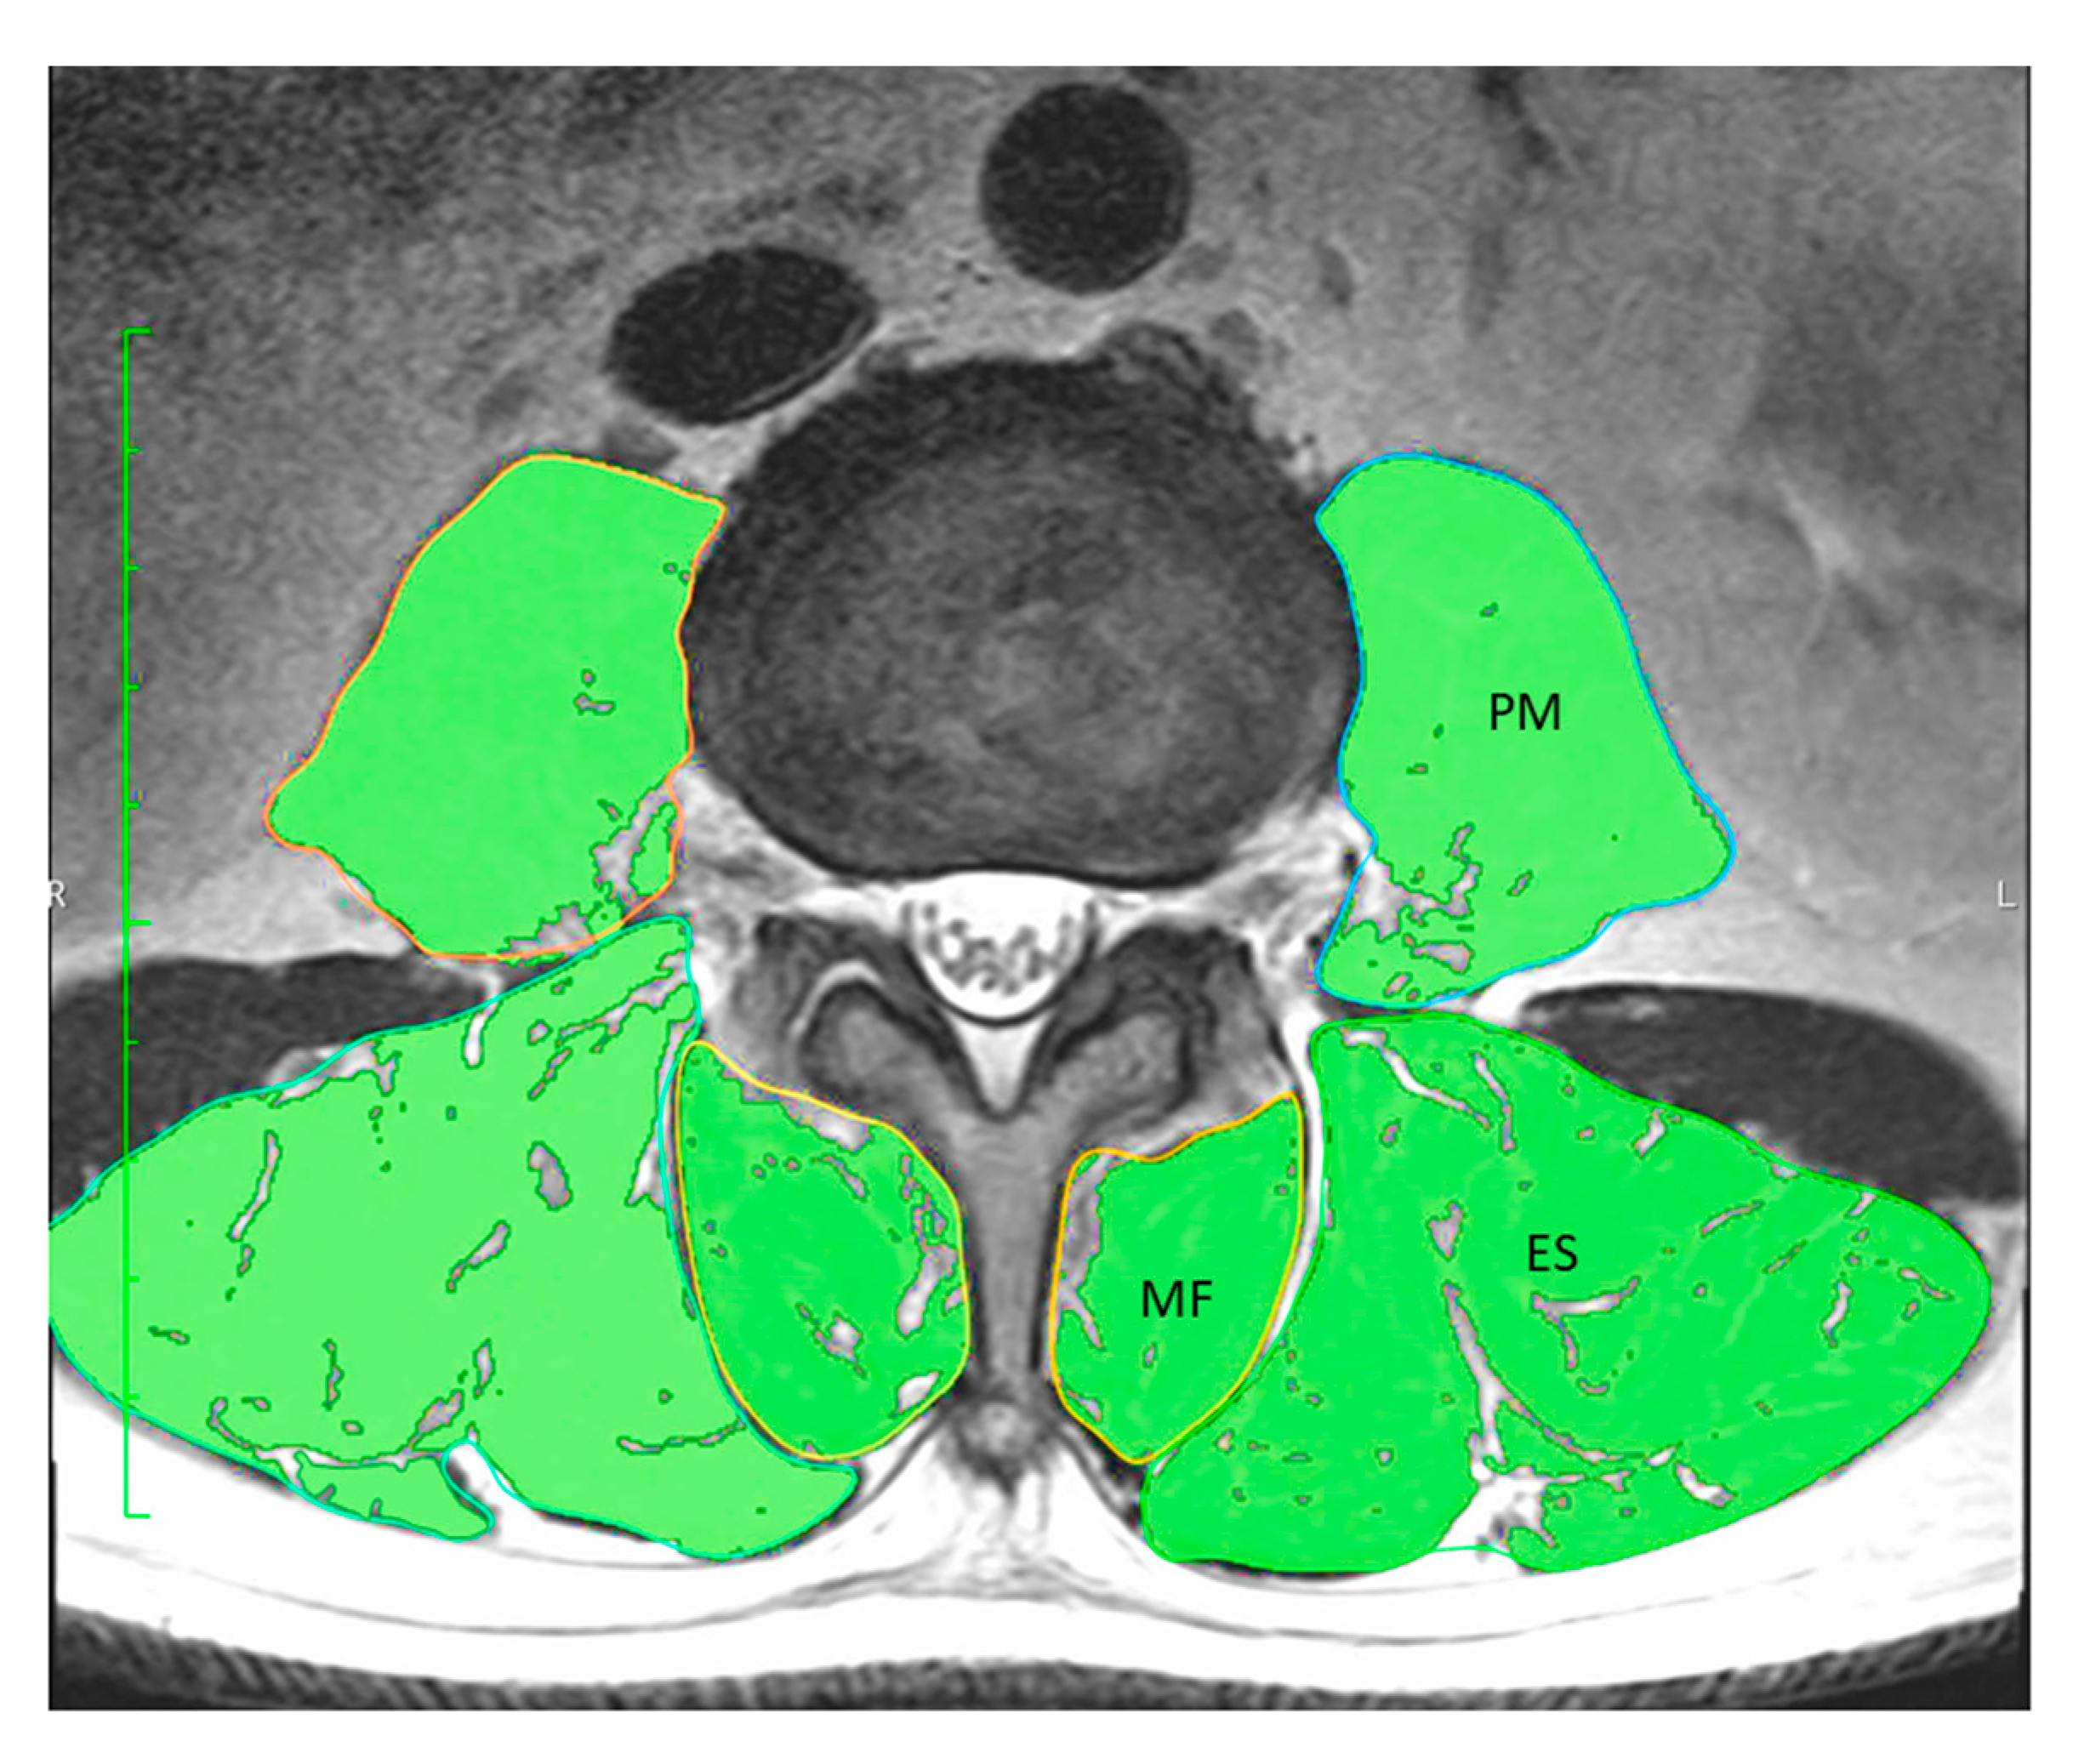

2.3.2. Quantitative Evaluation of Trunk Muscle on MRI

| ES | 28.26 (6.36) | 0.554 | <0.01 |

| ES (excluding intramuscular fat) | 23.25 (6.22) | 0.658 | <0.01 |

| MF | 8.93 (2.40) | 0.439 | <0.01 |

| MF (excluding intramuscular fat) | 6.27 (2.48) | 0.571 | <0.01 |

| PM | 16.29 (5.38) | 0.752 | <0.01 |

| PM (excluding intramuscular fat) | 15.17 (5.39) | 0.766 | <0.01 |

| Total PVM | 54.54 (11.56) | 0.746 | <0.01 |

| Total PVM (excluding intramuscular fat) | 44.70 (11.95) | 0.807 | <0.01 |